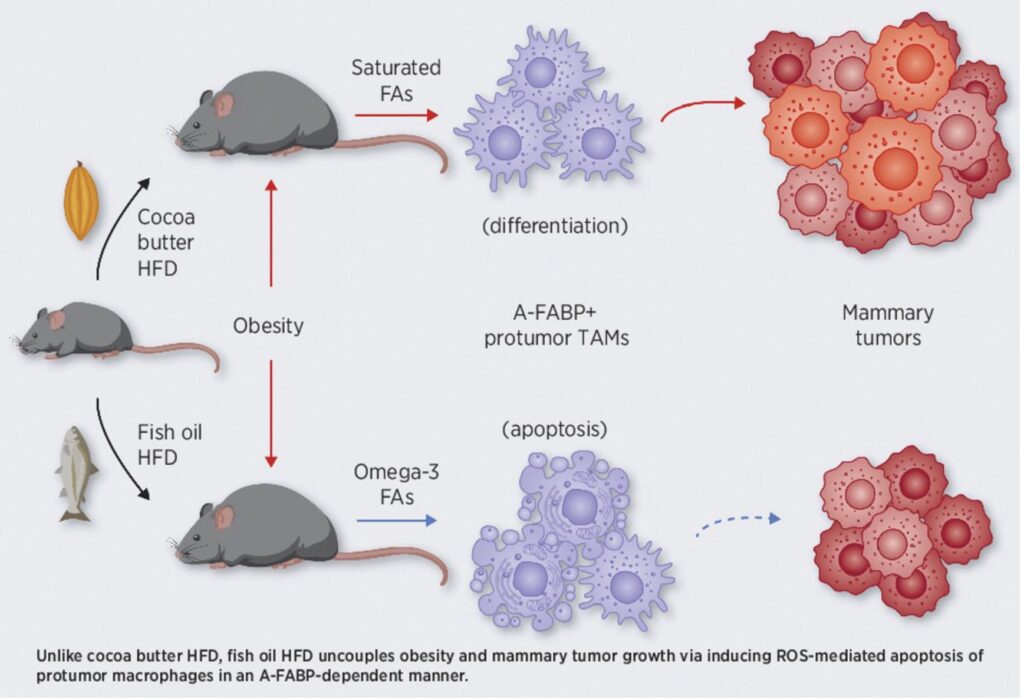

動物研究:魚油高脂飲食讓促癌免疫細胞明顯下降,腫瘤體積接近正常組

一篇來自《Cancer Research》(美國癌症研究協會,2020年)的動物研究(研究連結)指出:研究團隊設計了兩種「高脂飲食」的小鼠模型,一種以可可脂(飽和脂肪)為主,另一種以魚油(富含Omega-3脂肪酸)為主,並長期餵食5個月。結果發現,兩組小鼠都同樣變胖(肥胖程度相近),但在腫瘤發展上卻出現關鍵差異:可可脂組的乳腺腫瘤明顯加速成長,而魚油組則沒有出現肥胖帶來的腫瘤惡化現象,甚至腫瘤體積接近正常飲食組。

進一步機制分析發現,魚油中的Omega-3脂肪酸(如EPA、DPA)會促使一類「促腫瘤巨噬細胞」產生大量活性氧(ROS),進而引發這些細胞自我凋亡(死亡)。簡單來說,魚油不是直接殺癌細胞,而是先削弱腫瘤的「幫兇」免疫細胞,讓腫瘤失去成長支持。此外,這個過程依賴一個關鍵蛋白A-FABP,負責將脂肪酸送進細胞內進行氧化反應,啟動這條「ROS→細胞死亡」路徑。

整體結論是:不是所有高脂飲食都一樣危險。即使同樣導致肥胖,不同脂肪種類會影響免疫環境與腫瘤發展。魚油中的Omega-3脂肪酸,透過改變免疫細胞命運,可能在機制上降低肥胖與癌症之間的連動關係,提供一個全新的營養與癌症預防觀點。